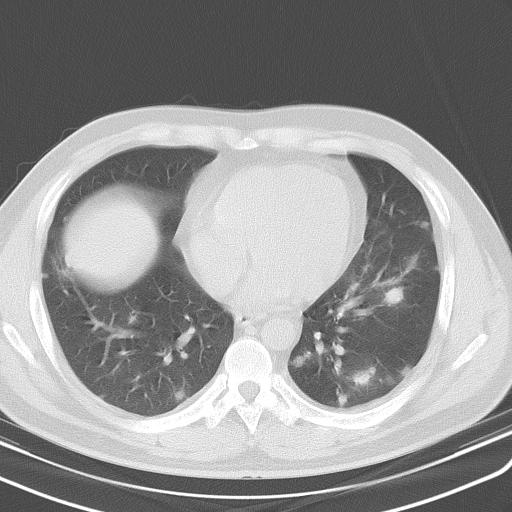

患者男性 35 主因发热咳嗽四天,血象不高,心肺听诊未见异常,无其它病史及传染病接触史。

一周后复查胸片基本正常

补充一下各种检查结果,病人无痰,胸闷,ppd及结核抗体阴性,wbc7.5x10的9次方,血沉22mm/h,crp及抗链o阳性。

哦cea8

双肺及胸膜下见多发结节影,最大直径约0.4,内密度均匀,中纵隔腔静脉后见小淋巴结影。

首先考虑转移瘤,建议查原发灶;

经一周抗炎抗病毒治疗复查胸片示病变大部吸收,基本恢复正常,未做气管镜检查,考虑为炎性变或霉菌感染。